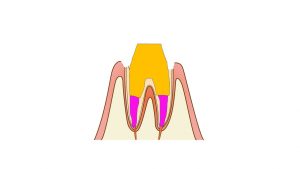

半年から1年くらいかかりますが、ドックベストセメントのミネラル成分が歯の内部に侵透し、(意図的に)取り残した虫歯を再石灰化(強く)していきます。ドックベストセメントの薬効成分は永続的と言われています。

取り残した虫歯が再石灰化され最低限の治療で虫歯を治すことが出来ます。

あくまでもイメージ画像の比較ではありますが、ドックベストセメントによる虫歯治療は、歯をほとんど削らず虫歯を治療できることがお分かりいただけたと思います。今までの保険のきかない治療では詰め物や被せものを高価なものにするだけで、歯を削ることについては、保険の治療と大差ありませんでした。しかし、ドックベストを使用した治療では歯を削る量=歯の寿命で大差が出てきます。虫歯の治療が必要な場合はご検討をおすすめいたします。